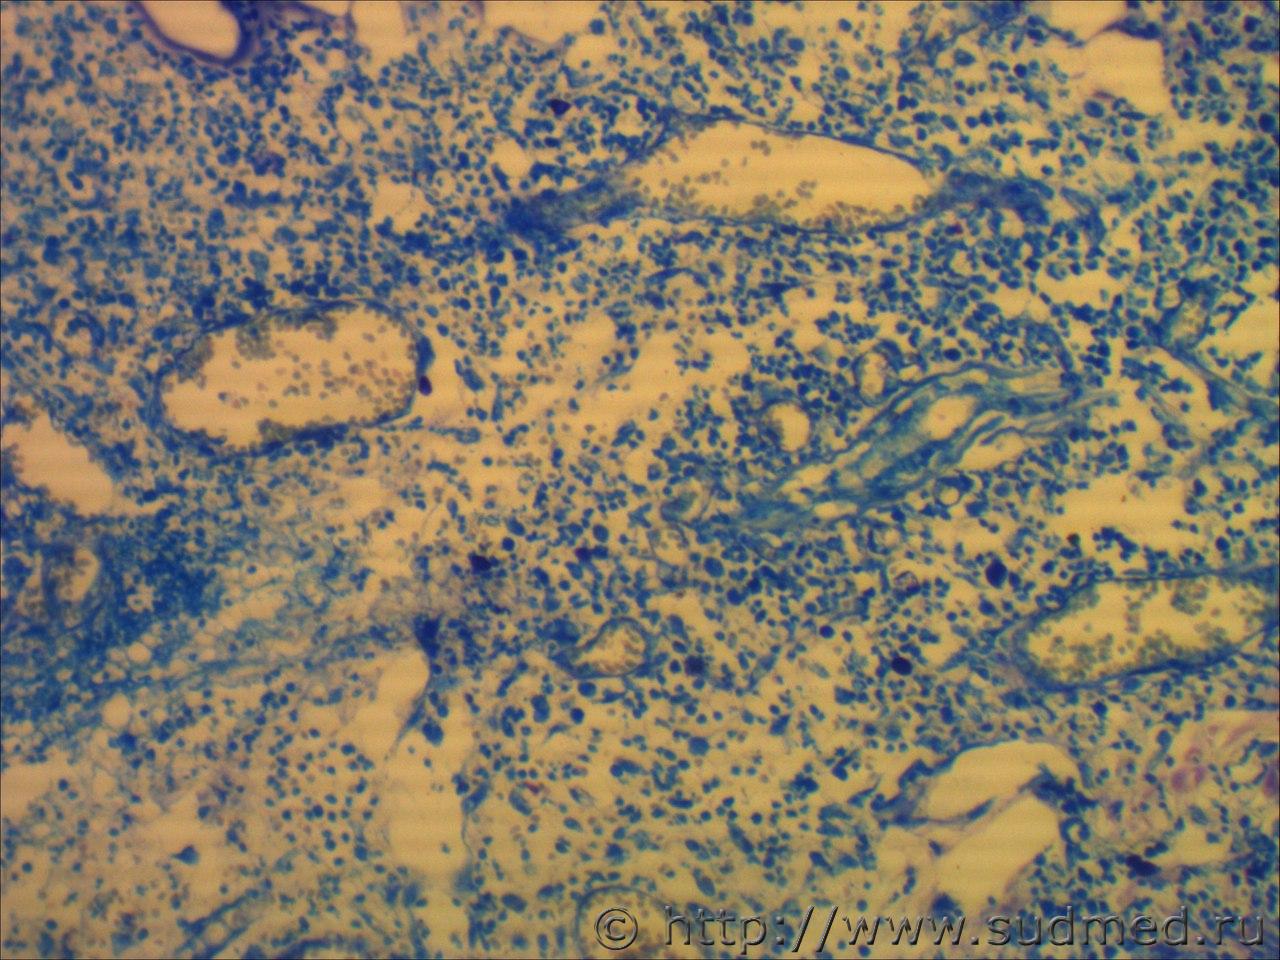

вижу что тяжи клеток эпидермиса проникающие в глубокие слои кожи и подлежащие ткани. Размеры клеток варьируют, слабовыраженное ороговение отдельных клеток, обильный воспалительный инфильтрат, пласты эпителиальных клеток в виде гнезд отделяются от эпидермиса. Склонен к ПКР

круглоклеточная опухоль, эпителий без патология

Фото низкого качества.

Попробую предположить,что на фото плазмоцитома и псевдокарциноматозная гиперплазия.